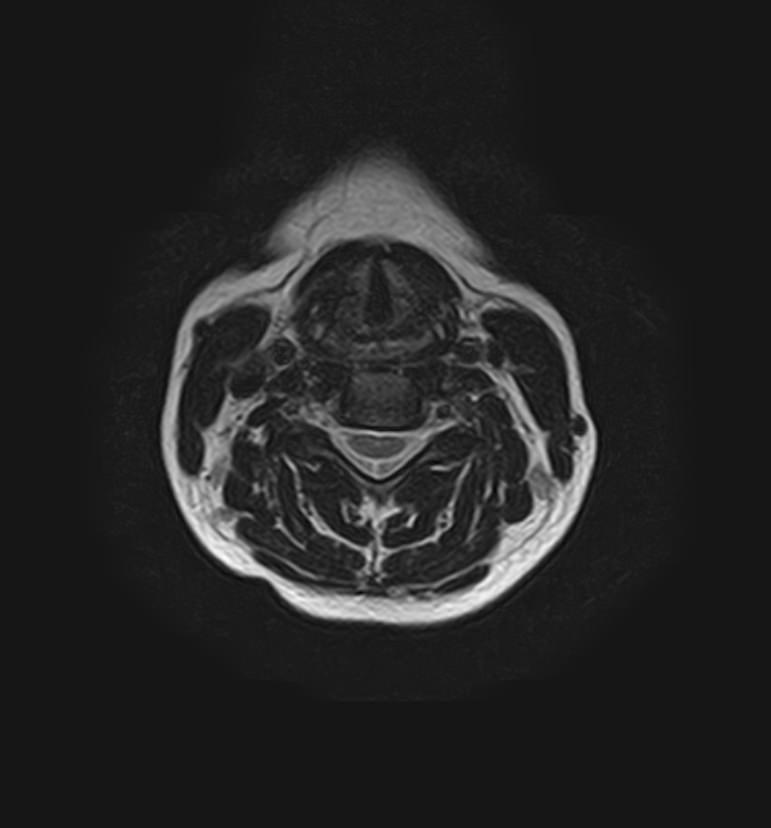

Шейный отдел позвоночника — это самый подвижный сегмент позвоночного столба, который испытывает повышенные нагрузки, подвержен травмам и развитию различных заболеваний. В эту анатомическую область входит 7 верхних позвонков, спинной мозг с отходящими от него нервными корешками.

Сканирование проводится на современном высокопольном магнитно-резонансном томографе закрытого типа TOSHIBA VANTAGE TITAN 1,5 Тесла. Магнитно-резонансный томограф производит послойное сканирование исследуемой зоны в разных плоскостях, затем при помощи компьютерных программ преобразует полученные данные в трехмерные изображения. При этом кровеносная система реконструируется как вместе с окружающими тканями, так и отдельно без них.

Что показывает МРТ головного мозга + МРТ шейного отдела позвоночника + МР-ангиография шеи и головного мозга

В рамках проведения данного комплексного исследования можно выявить:

• остеохондроз, спондилоартроз, спондилез, межпозвонковые грыжи, унковертебральный артроз, сколиоз, усиленный или выпрямленный лордоз как нарушение статической функции позвоночника, травмы, аномалии позвоночника.